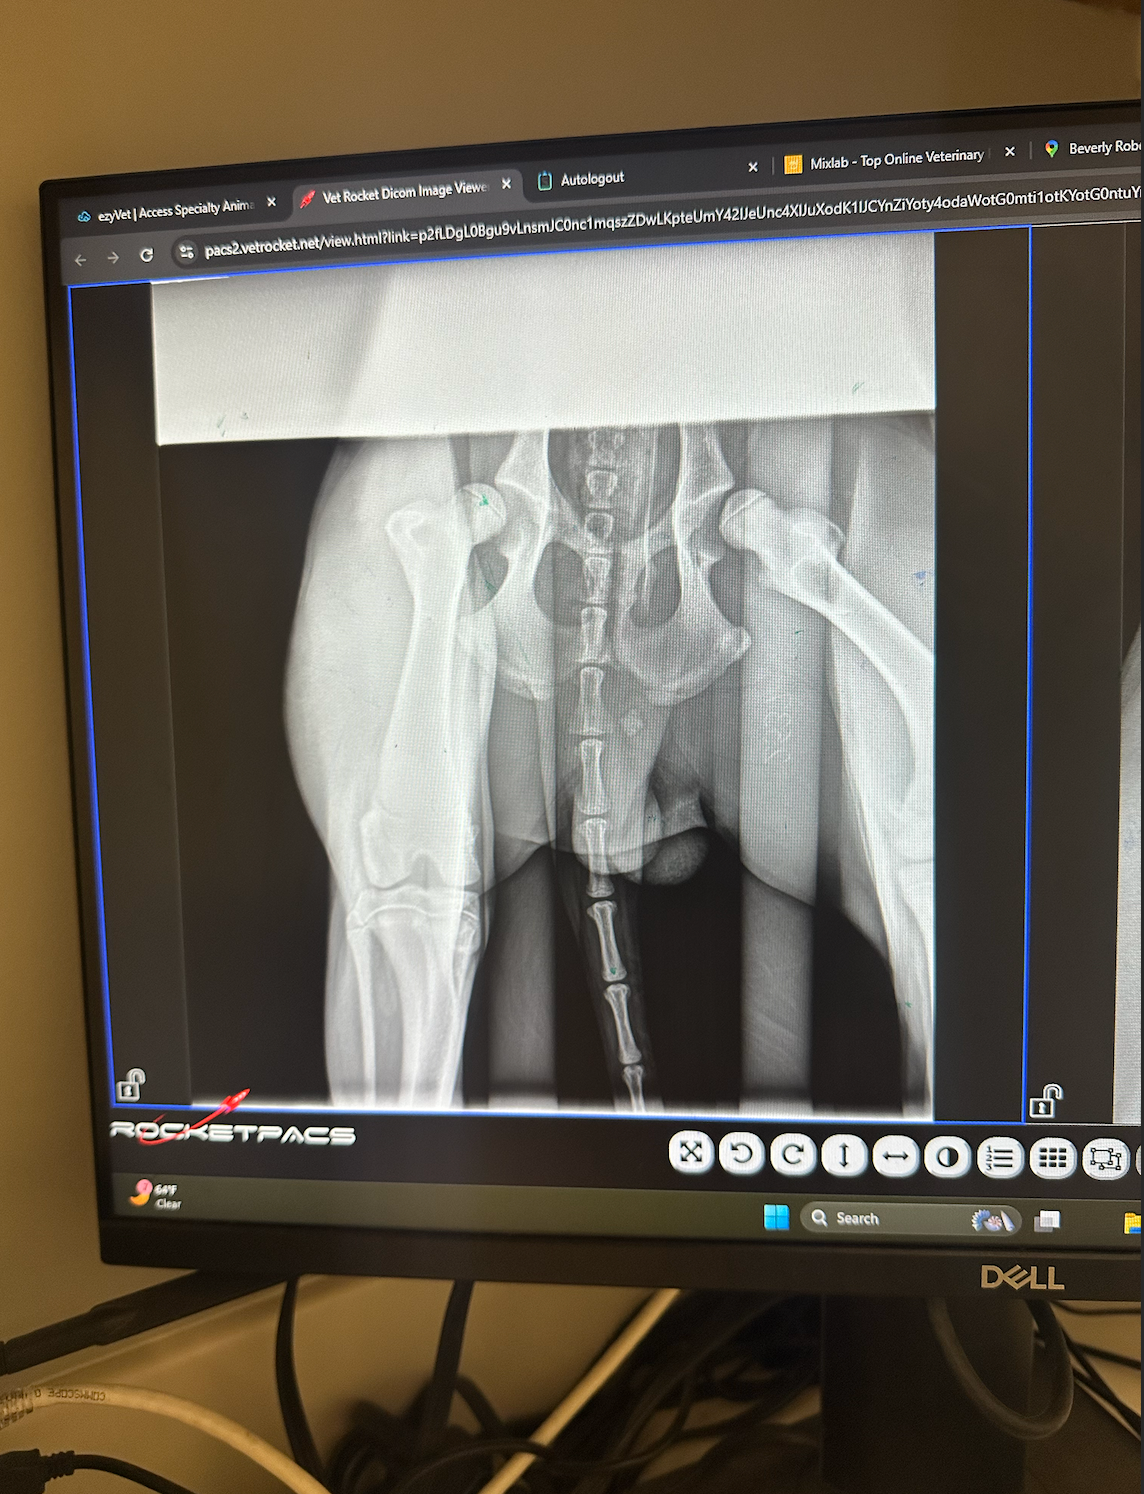

A few months ago, we noticed Sammy walking strangely. It became impossible to ignore how quickly he would slow down due to pain, compared to his healthy littermate Max. Sammy began limping more often, and we knew something was seriously wrong. An orthopedic specialist confirmed our worst fear: Sammy has severe hip dysplasia in both hips. His left hip is especially bad, and he will eventually need two total hip replacements. The initial quote for just one hip was $16,000, which completely shocked us.

We weren’t ready to give up. We spent weeks calling every orthopedic specialist and veterinary hospital we could find. Finally, we found hope at UC Davis Veterinary Teaching Hospital, which has an incredible reputation. We drove seven hours to get there, and the experience was night and day—the doctor spent a full hour reviewing X-rays with us, answering questions, and helping us understand Sammy’s situation. We felt cared for for the first time.